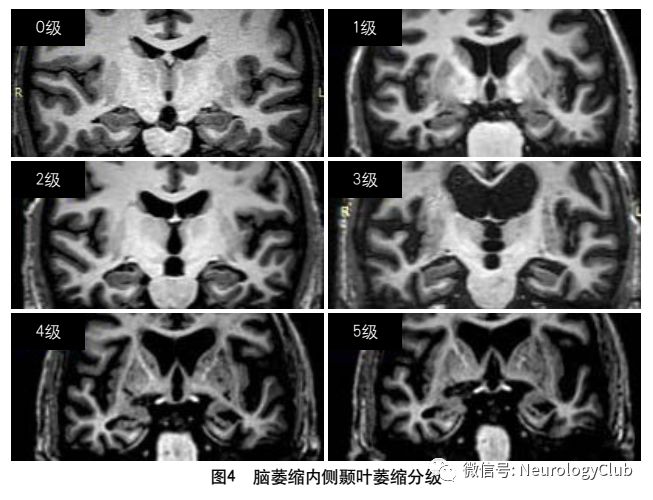

2013年的共识指南将脑萎缩定义为与特定的局灶性损伤,如脑外伤或脑梗死无关的脑容积减少脑萎缩可以是广泛的或局部的(如特定的脑叶或海马等特定区域),可以是对称或不对称的,亦可以是组织选择性的(如发生在白质等某一特定组织层)目前不同部位的脑萎缩有相应的诊断标准,全脑皮层萎缩分级用于评价全脑(图3);内侧颞叶萎缩分级主要评价颞叶内侧,重点是海马(图4);Koedam分级主要评价顶叶,尤其是扣带回和楔前叶(图5);Kipps/Davies分级主要评价额颞叶(图6)推测脑组织减少是由脑沟(周围)和脑室(中心)的脑脊液空间相对于颅内容积扩大所引起的